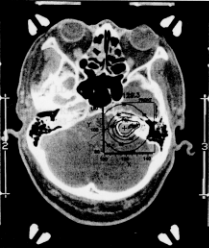

図3 聴神経鞘腫の線量計画(原論文4より引用)

図3に内耳道内への進展に伴う聴神経鞘腫に対する線量計画を示した。境界部の外側での線量の減衰はきわめて急速なため、周囲の脳組織への影響を最小限にしつつ、病変部組織を破壊するのに十分な線量を1回で照射することができる。通常の照射線量は脳動静脈奇形で20〜50Gy、聴神経鞘腫などの良性腫瘍で18〜20Gy(いずれも境界部の線量)であり、照射時間は通常15〜30分である。下垂体微小腺腫や機能外科の場合にはさらに大量の線量(40〜100Gy)を照射する。ちなみに、1回大量照射の効果は、従来の分割照射の約3〜5倍と考えられている。